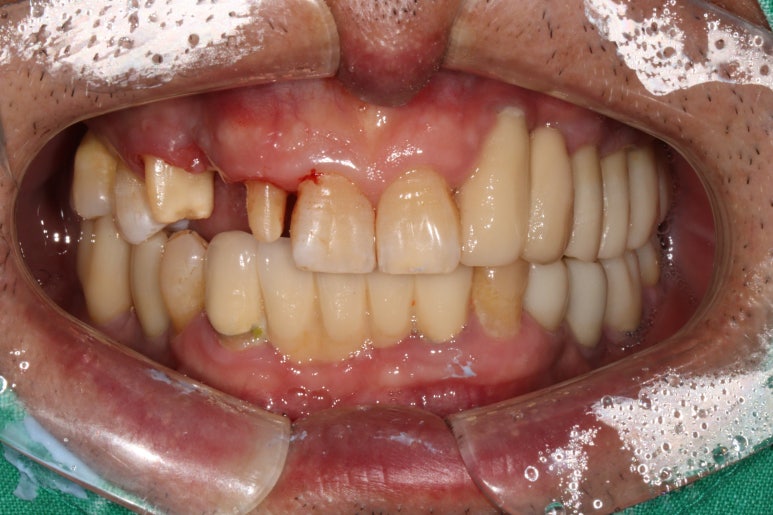

저희 병원에 오셨던 60대 남자 환자분입니다.

딱 봐도 구강위생상태가 좋지 않습니다...

잘 보시면 적절히 관리되지 않아 다수 축적되어있는 치태와 치석들을 쉽게 보실 수 있죠.

아~ 잇몸이 좋지 않았습니다. 그래서 스케일링과 잇몸치료 그리고 필요한 치아를 뽑고 임플란트 하기를 권해드렸죠. 이 분이 3년만에 저희 병원에 다시 오셨는데요.

오른쪽 위 송곳니가 잇몸이 붓고 흔들려서 뽑고싶어요.

이번에 저희 치과로 오신 이유는 바로 이 송곳니 때문이었습니다.

딱 봐도 만성 치주염이 너무 심해서 고름이 맺혀있는 것을 보실 수 있죠..

이미 병적 치아 이동 상태 (pathologic migration)이 심해서 치아는 내려오고 치아 사이 틈은 더 벌어진 상황.

속된말로 치아가 둥둥 떠있었습니다.

보시면 치아의 병적 이동으로 이미 자기 자리에서 한참 이탈해버린 오른쪽 위 송곳니를 보실 수 있습니다.